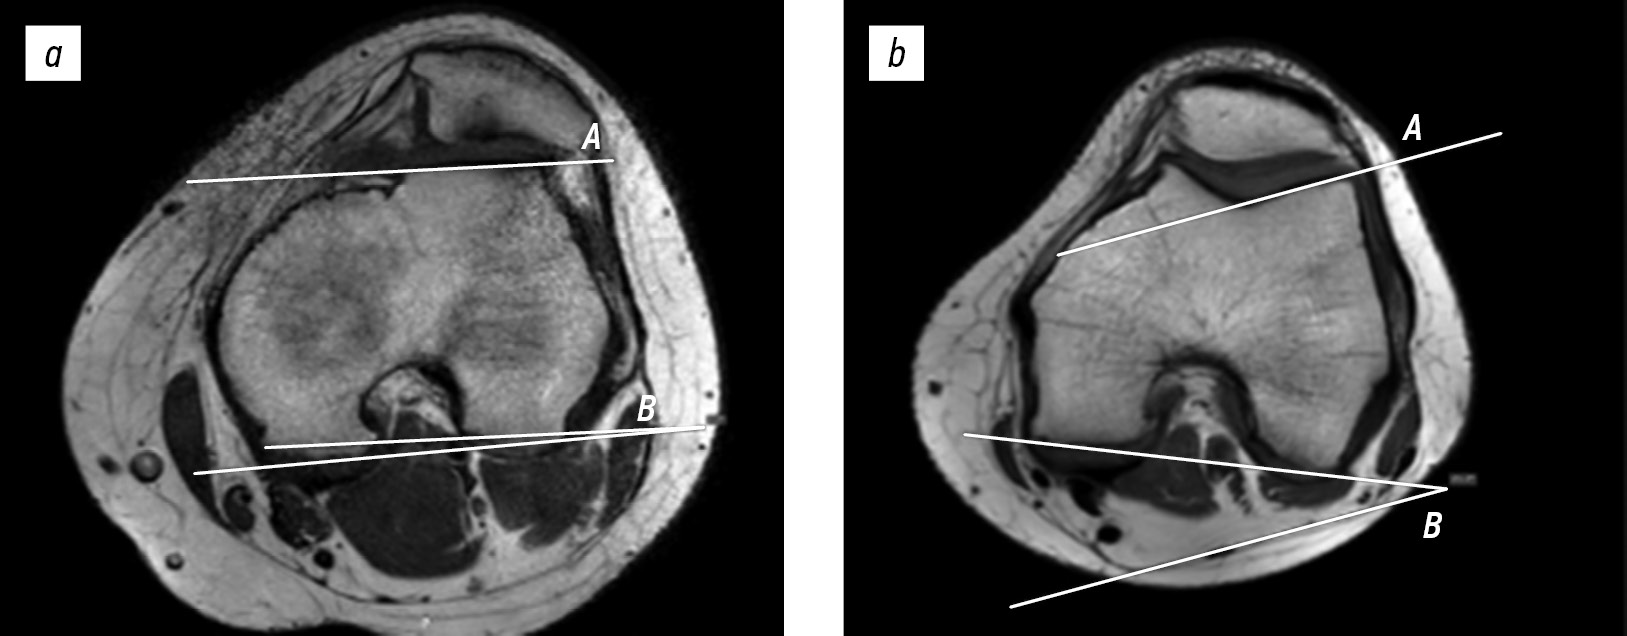

Trochlear facet asymmetry was evaluated on axial MRI images without fat suppression, using the first slice on which the articular cartilage was visible. Trochlear groove asymmetry was measured as the ratio of the medial facet to the lateral facet. The length of the medial facet (M) and of the lateral facet (L) were measured to obtain facet asymmetry; the length of the medial facet was divided by the length of the lateral facet and expressed as percentage (M/L × 100%). A ratio of the trochlear facets below 40% was indicative of trochlear dysplasia (Fig. 2) [13].

Fig. 2. Trochlear facet asymmetry index on magnetic resonance imaging: (a) 16-year-old female patient with patellar instability (33%) and (b) 17-year-old female patient with anterior cruciate ligament injury (75%). M, medial facet length; L, lateral facet length.